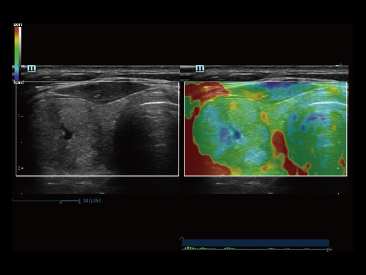

Resona 7

Mindray? ??? ??? ?? ??? ???? ??? ?? ??? ??? ????? ??? ????. ?? ???? ZONE Sonography? ??? ???? ?? Resona 7? ??? ZST+ ???? ?? ?? ? ?? ??? ????? ?? ??? ??? ??? ? ?? ????.

?? Resona 7? ???? ??? ?? ???? ??? ??? ???? ??? ?? ???? V Flow? ?? CNS ??? ?? 3D ??? ???? ?? ???? ?? ??? ?? ?? ?? ??? ??????. ???? ??? ??? ?? ?? ??? ??? ?? ?? ??? ??? Resona 7? ??? ???? ???? ??? ??? ??? ????.